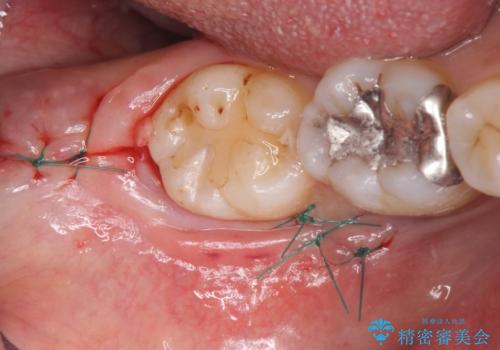

歯ぐきの形を整え、外れにくい被せ物を装着

歯の高さを出すための親知らず抜歯と歯肉切除